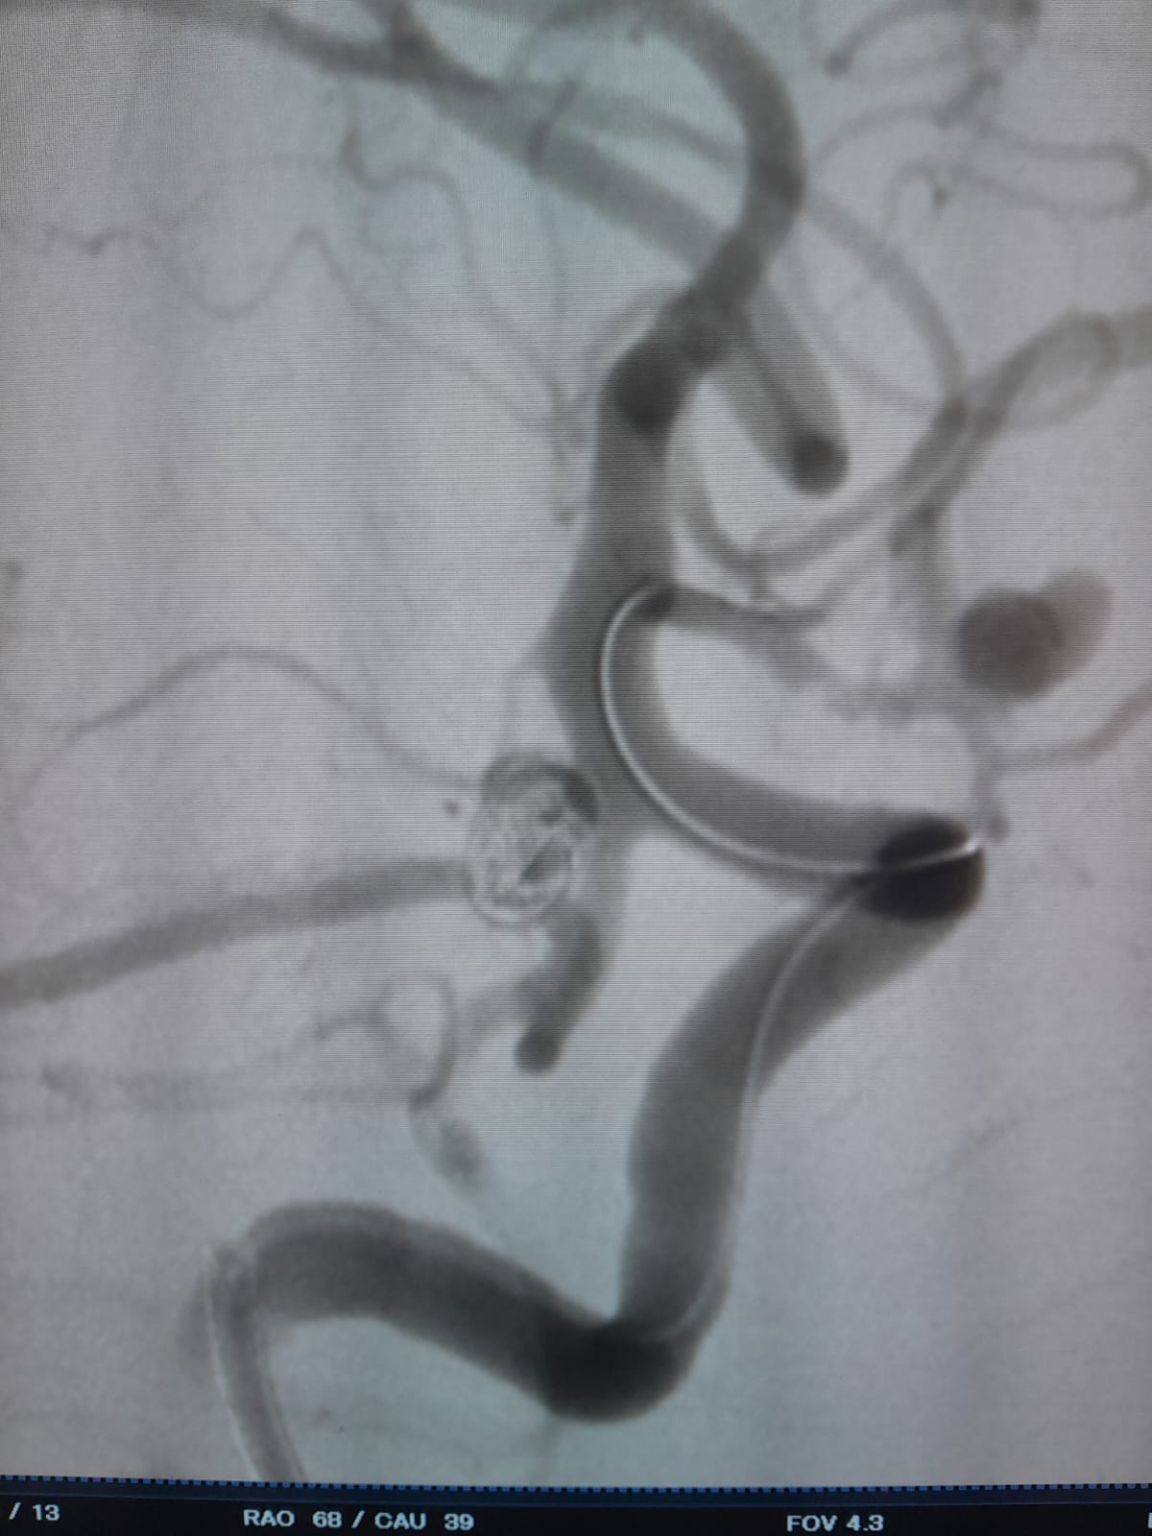

Al paziente è stato diagnosticato un aneurisma sacculare dell'arteria comunicante anteriore (AComA) appena scoperta e un aneurisma dell'arteria comunicante posteriore (PComA) che era stato precedentemente trattato con embolizzazione della bobina. L'imaging di follow-up ha rivelato il riempimento residuo dell'aneurisma PComA, che richiede un intervento aggiuntivo.

Aneurisma dell'arteria comunicante posteriore (ri-trattamento)

Durante il follow-up, è stato notato un riempimento residuo nell'aneurisma dell'arteria comunicante posteriore precedentemente trattato. Il team è rientrato nel sito utilizzando Frepass®Microcatetere monouso (TJMC18 Plus) e implementato con successo un Nuva®Flow Diverter (TJED-D-4.5-16), che ha dimostrato l'apposizione ideale della parete e l'eccellente deviazione del flusso, portando a risultati del trattamento altamente soddisfacenti.